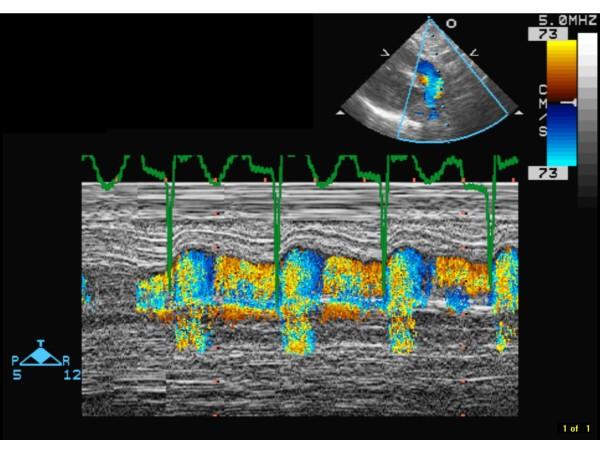

新生儿肝衰竭是一种罕见但常致命的疾病。唐氏综合征通常与严重的婴儿期肝病无关。如果唐氏综合征婴儿存在肝功能障碍,其原因可能是肝浸润的造血细胞引起的短暂骨髓增生异常,且可能伴有继发性血色素沉着症。唐氏综合征新生儿肝衰竭的另一个不太常见的原因是新生儿血色病(NH);在文献中已有 9 例唐氏综合征合并 NH 的报道。NH 是一种罕见的、严重的先天性肝脏疾病,其特征为新生儿肝衰竭和肝内及肝外铁蓄积,网状内皮系统不受累。NH 是新生儿肝衰竭最常见的原因,也是新生儿肝移植最常见的适应证。尽管已经报道了成人和大龄儿童肝衰竭的并发症为门肺高压(PPH),但在任何病因引起的新生儿肝衰竭中尚未见报道。这可能是由于新生儿肝衰竭的罕见性、诊断延迟和高死亡率所致。认识到 PPH 的重要性在于它可以通过肝移植逆转,但同时增加了术后死亡率的风险。因此,早期诊断 PPH 至关重要,以便早期干预可以提高成功进行肝移植的机会。我们首次报道了一例唐氏综合征婴儿因 NH 引起的肝衰竭伴门肺高压。